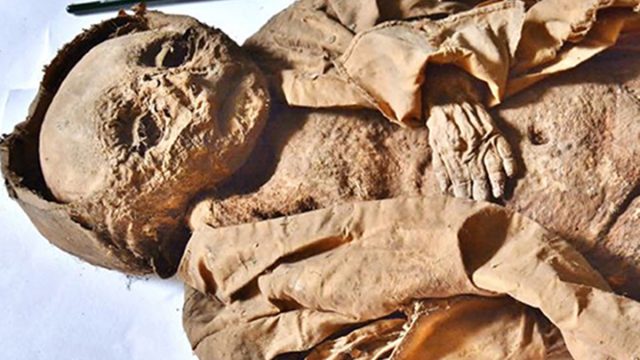

The child was found in Hellmonsödt, Austria, in a wooden coffin inside a crypt for the Counts of Starhemberg. It belonged to an upper-class family of the 17th century, one of the oldest aristocratic families in the country. Researchers from Germany's Academic Clinic Munich-Bogenhausen determined that the boy was likely Reichard Wilhelm, who died in 1625 or 1626.

The crypt contained several members of the family. All of them were buried in ornate metal coffins—except for the toddler, whose simple wood casket was unmarked. What led to the child's demise at such a young age? Read on to find out what the scientists discovered.

According to the study, published this week in the journal Frontiers in Medicine, the boy's body was well-preserved and had become mummified, allowing researchers to analyze its soft tissue. To do this, they used a CT scanner.

The research team studied the child's teeth and measured his bones, which indicated he was between 12 months and 18 months old when he died. The boy had dark hair and was overweight for his age, suggesting he was well-fed.

However, the CT scan revealed that his ribs were deformed, indicating a metabolic bone disease. They had developed in a pattern called a "rachitic rosary," a condition in which knobs of bone develop at the junction of ribs and cartilage. It's usually seen in severe cases of rickets or scurvy. The scan also revealed inflammation of the lungs characteristic of pneumonia.

To the researchers, this indicated that although the toddler had been fed enough to put on plenty of weight, he was still malnourished. They suggest he developed a vitamin D deficiency after being kept inside and away from sunlight.